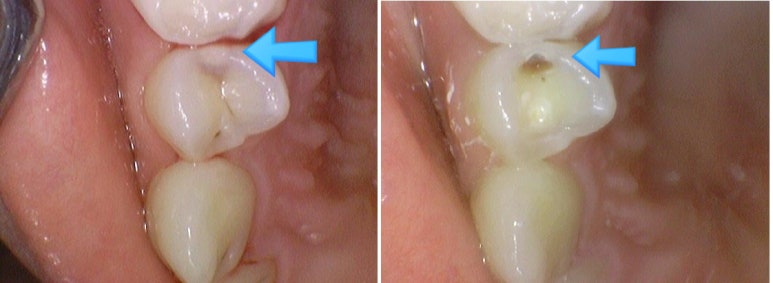

겉에서는 크게 보이지 않지만 치아를 삭제해보면 깊은 충치

환자분이 보기에는 겉에서는 특별히 검게 보이지 않지만

치아를 삭제해보면 깊은 충치인 경우가 많습니다.

엑스레이와 눈으로 보는 시진을 바탕으로 원장님의 검진에 따라 어떤 치료가 진행될지 결정됩니다.

저희 치과는 충치가 깊은 경우 치료 전과 치료 중간중간 구강내 사진을 많이 찍는데요

환자분께 이런 부분에 충치가 깊게 있었다 설명드리고,

치료 후에도 환자분이 관리할 수 있게 만들기 위해서 입니다.